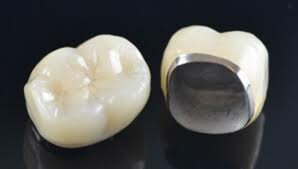

• Corona Metal Porcelana

Corona Metal Porcelana

• Corona sin Metal

McLean and Hughes crean la corona sin metal, utilizando un núcleo de matriz de vidrio de 40-50% en peso de A12 O3 para fabricarla